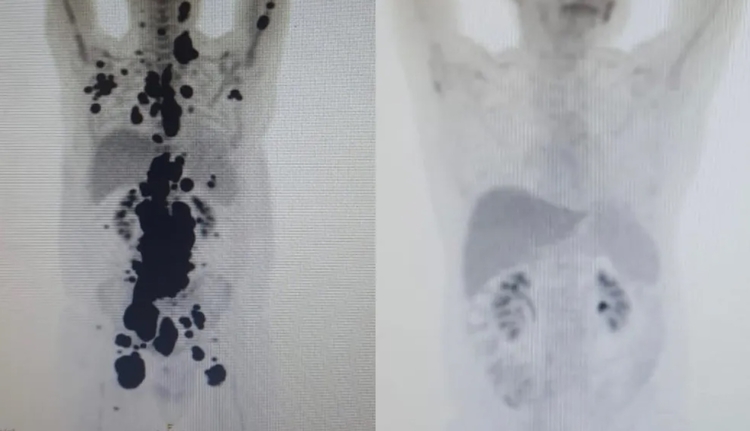

Imagem mostra antes e depois do tratamento do paciente Paulo Peregrino / Foto: Arquivo pessoal

Um homem com câncer há 13 anos teve remissão completa em apenas um mês ao passar por tratamento com terapia celular, em São Paulo. O teste foi feito pela Universidade de São Paulo (USP) em parceria com o Instituto Butantan e o Hemocentro de Ribeirão Preto.

Entre eles, Paulo Peregrino, de 61 anos, que estava há 13 anos lutando contra o câncer, teve remissão completa um mês após ser submetido ao tratamento. O paciente estava prestes a receber cuidados paliativos quando foi selecionado para o teste.